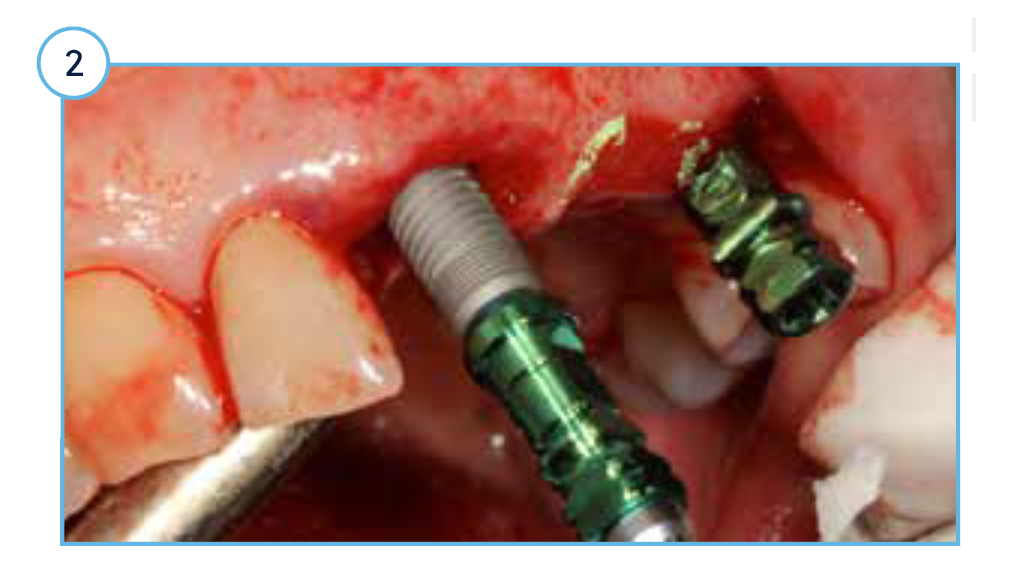

TSVT Implants (4.1 mm x 16 mm) with attached fixture mounts threaded into the prepared extraction sockets.